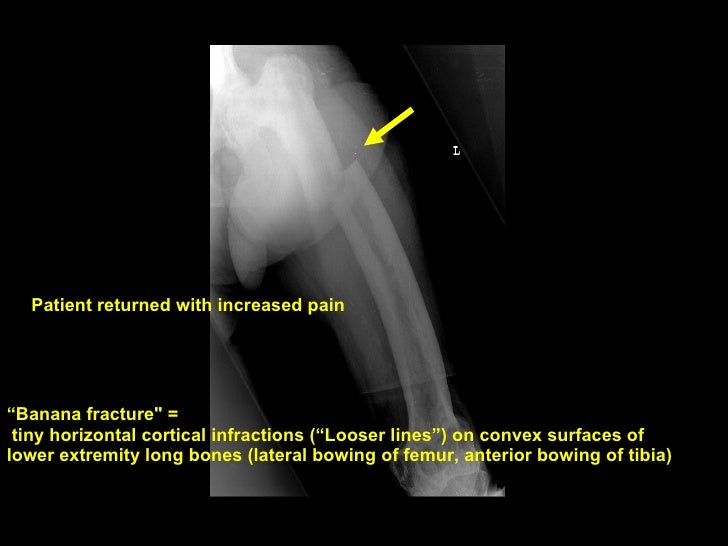

Radiology Rounds: Elderly Male With Leg Pain